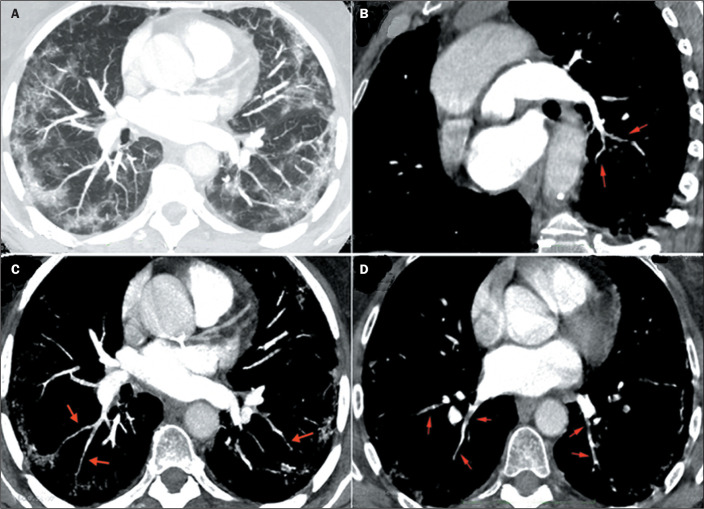

Objective: The purpose of this study was to evaluate the characteristics and meaning of the vessel wall irregularities sign, observed on computed tomography angiography of the pulmonary arteries of patients with coronavirus disease 2019 (COVID-19) pneumonia.

Results: The vessel wall irregularities sign was observed in 50 (76.9%) of the 65 patients with COVID-19. Among those 50 patients, the vascular involvement was predominantly mixed (arterial and venous) in 43 (86%), subsegmental in all 50 (100%), segmental in 13 (26%), bilateral in 46 (92%), affecting 4-5 lobes in 35 (70%), mainly in the right lower lobe in 46 (92%), and mainly in the left lower lobe in 44 (88%).

Conclusion: The vessel wall irregularities is a prevalent sign of vascular involvement in patients with COVID-19.